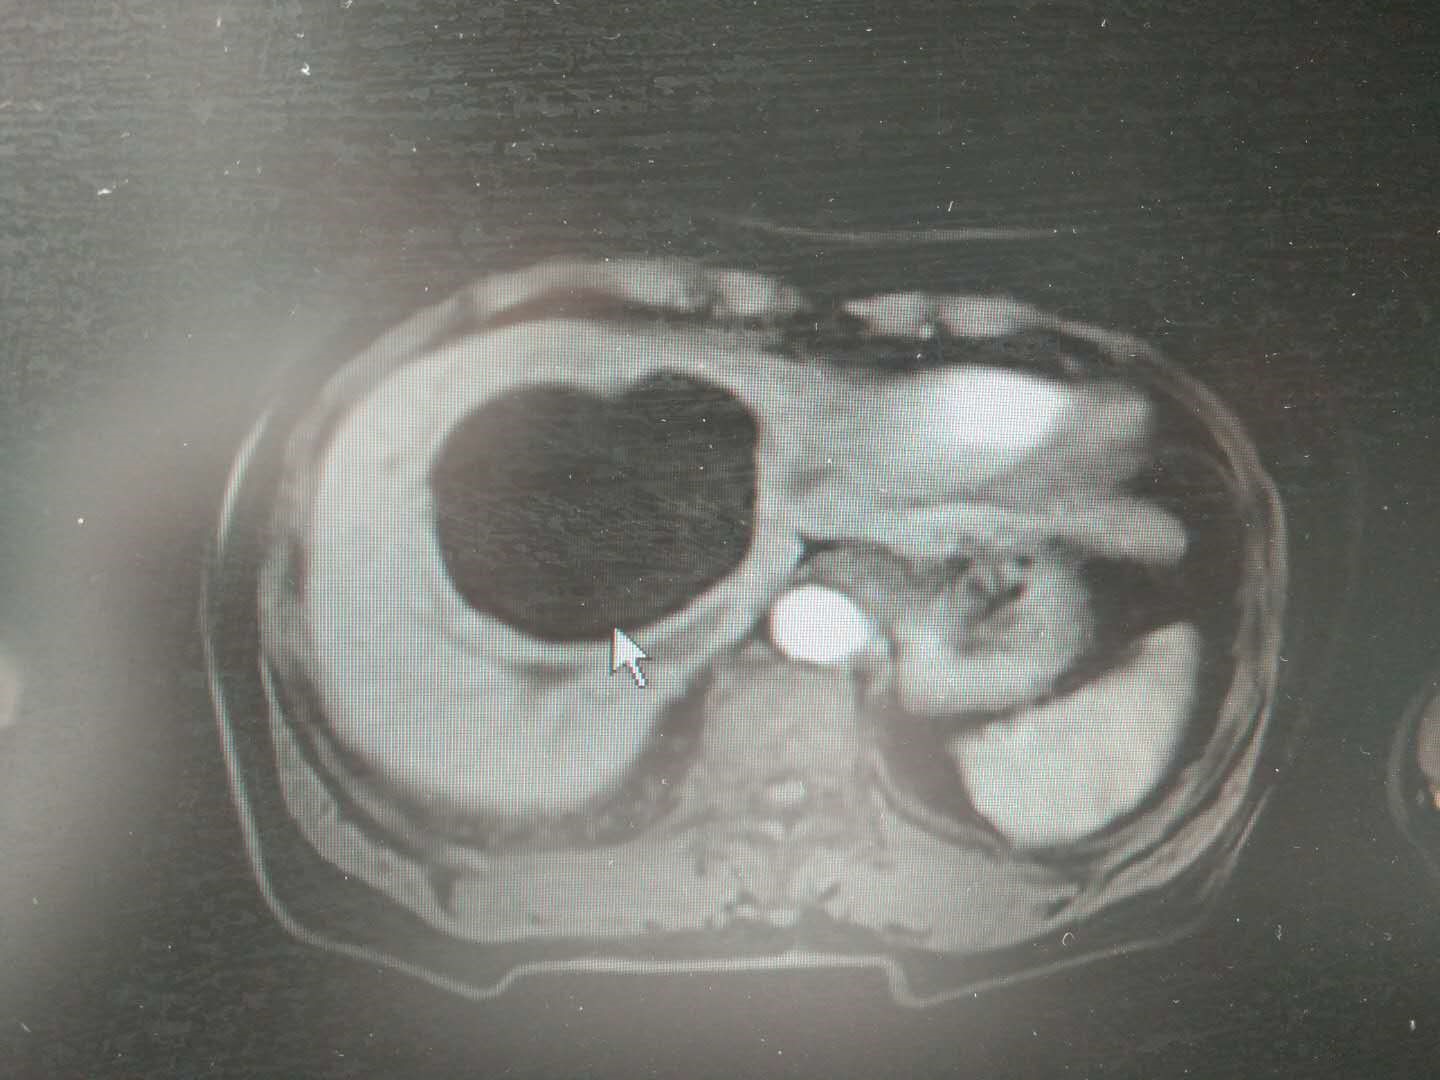

六年前体检时,姚女士被发现右肝患有囊肿,医生建议每年复查腹部B超观察变化,就这样,她眼看着囊肿直径从5.9cm*157.5px增大到了如今的204.99999999999997px*165px,终于忍不住了。

肝囊肿是起源于肝内迷走胆管的一种滞留性囊肿,属于先天发育异常。它的生长一般较为缓慢,多数患者无症状,但巨大的肝囊肿可出现明显的压迫症状。合并感染可出现畏寒、发热、腹痛等类似于肝脓肿的病症。

肝囊肿的治疗视其大小、性质及有无并发症而定。一般直径大于125px,并出现压迫症状者则有手术指针。